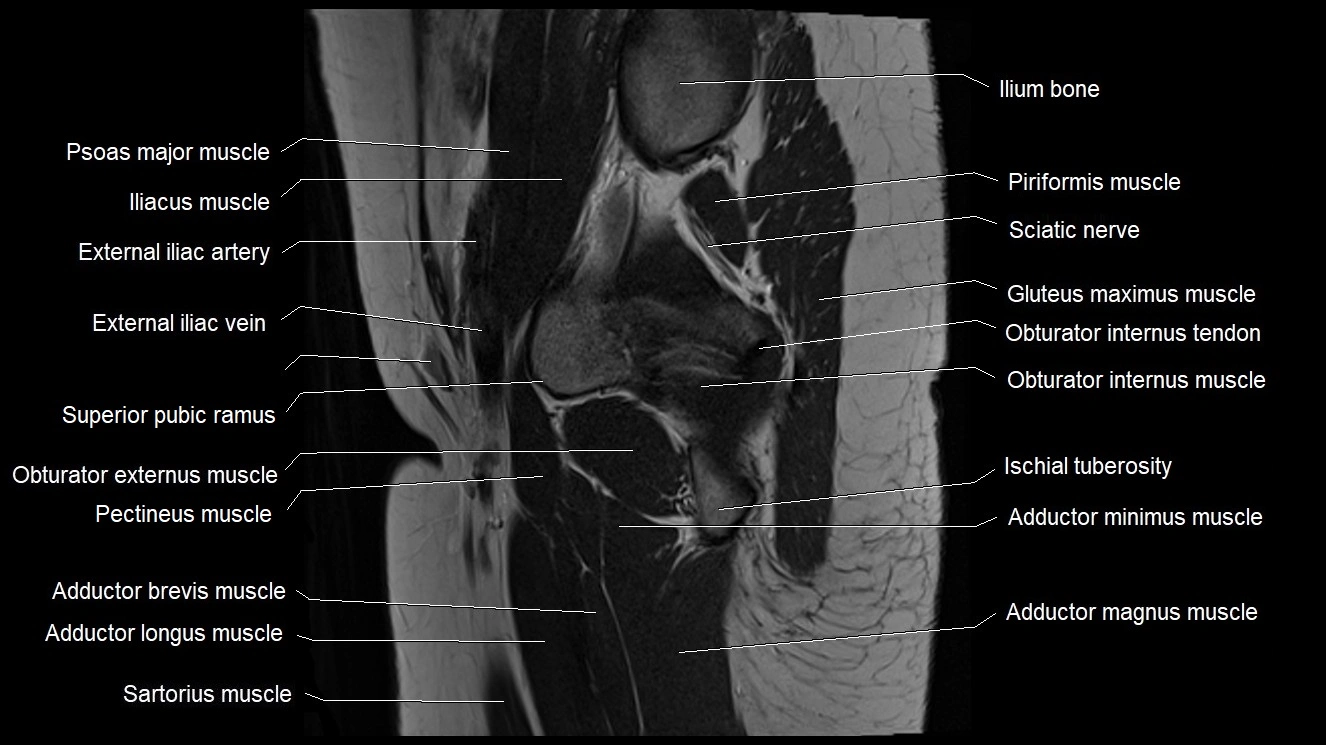

- Adductor brevis muscle

- Adductor longus muscle

- Adductor magnus muscle

- Adductor minimus muscle

- External iliac artery

- External iliac vein

- Gluteus maximus muscle

- Ilium bone

- Ischial tuberosity

- Ischium bone

- Obturator externus muscle

- Obturator internus muscle

- Obturator internus tendon

- Pectineus muscle

- Psoas major muscle

- Rectus femoris tendon (Proximal tendon of rectus femoris)

- Sartorius muscle

- Superior pubic ramus